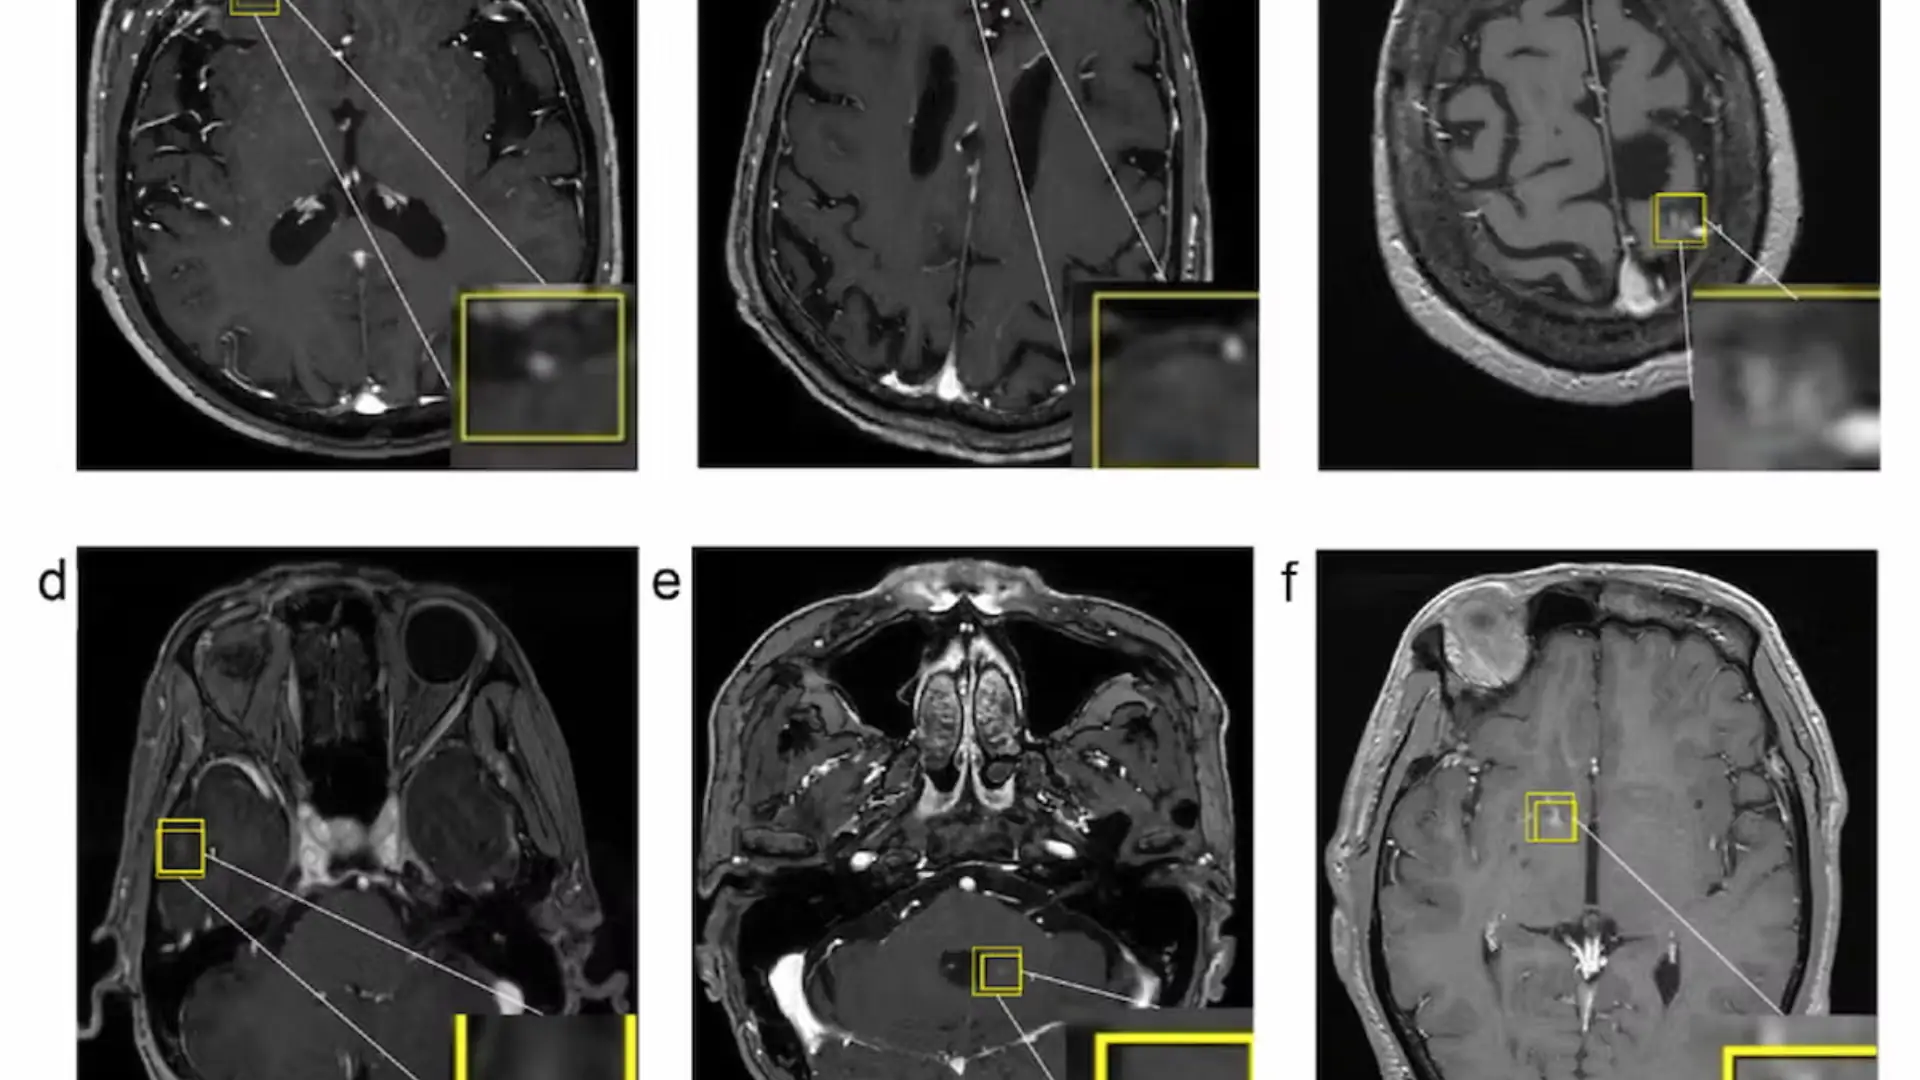

La integración de micro-ecografía y MRI en la ablación focal con láser presenta importantes implicaciones para la práctica clínica.

La mejora en la localización tumoral permite que el tratamiento se dirija específicamente a las áreas afectadas, reduciendo la probabilidad de recurrencias y minimizando el daño a tejidos sanos.

Esta precisión se traduce en una reducción de intervenciones adicionales y en una optimización del flujo de trabajo clínico, lo que es especialmente relevante en entornos con acceso limitado a especialistas en imagenología.

A pesar de los resultados prometedores, se identifican desafíos en la monitorización simultánea de temperatura durante el procedimiento, lo que podría aumentar el riesgo de complicaciones como la fístula retroprostática.

La incorporación de técnicas de hidrodesinfección emerge como una solución para mitigar estos riesgos, especialmente en casos de tumores en zonas bilaterales o periféricas. Además, la adaptación de estos protocolos en centros clínicos requiere formación específica y una estrecha colaboración entre radiólogos, urólogos y especialistas en tecnología médica.